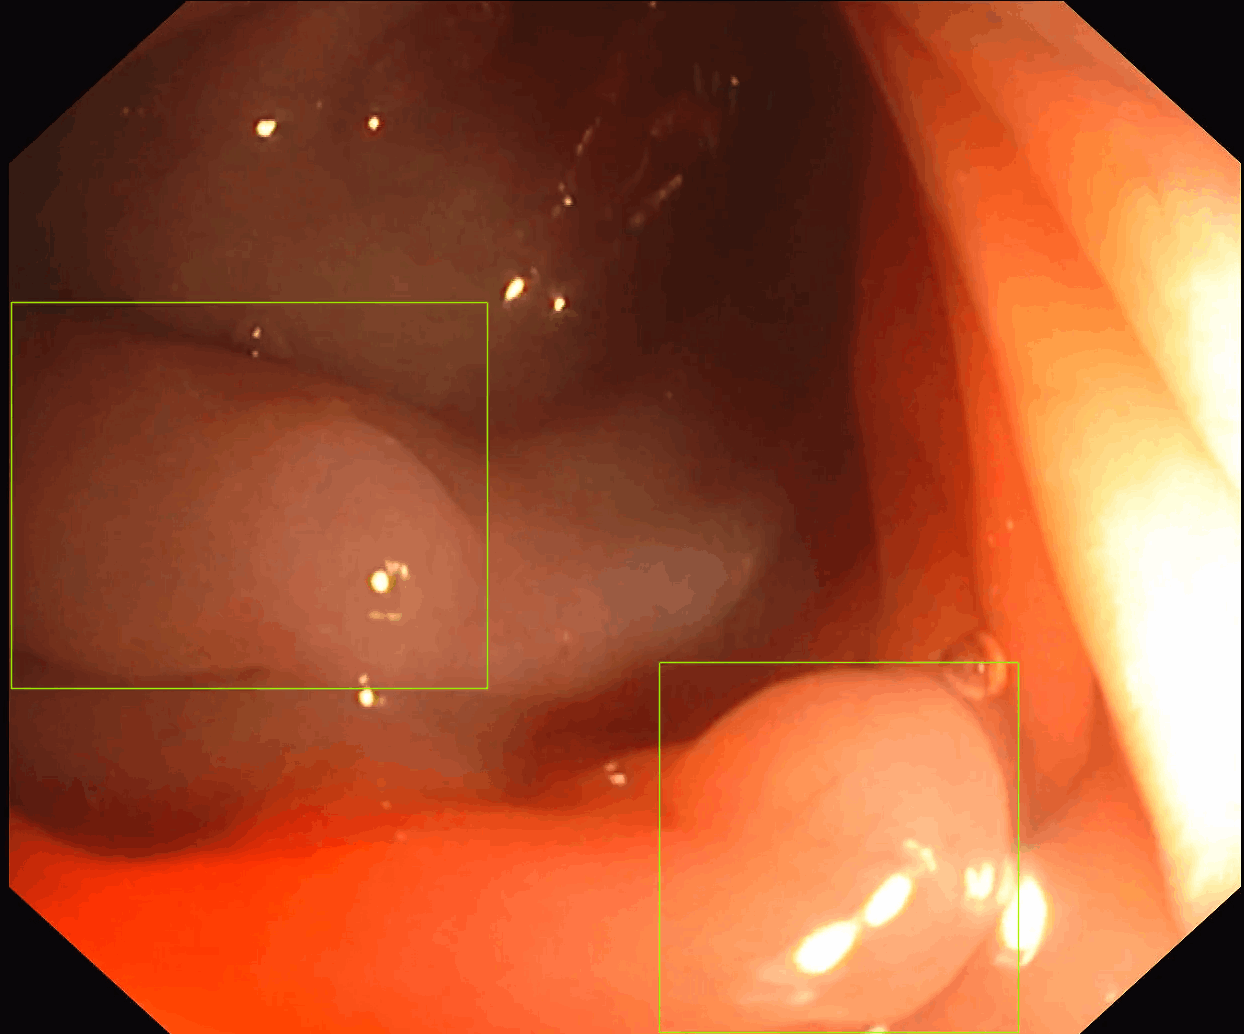

Our first product, SofiOne, is undergoing clinical validation as a decision support tool for the diagnosis of all polyp findings in colonoscopy.